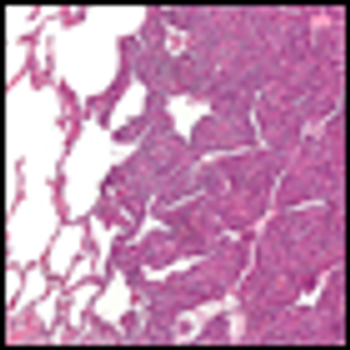

This slide show features a CT image, and pathology images of gastrointestinal stromal tumors (GISTs) arising in the stomach using H&E, CD34, and c-Kit staining.